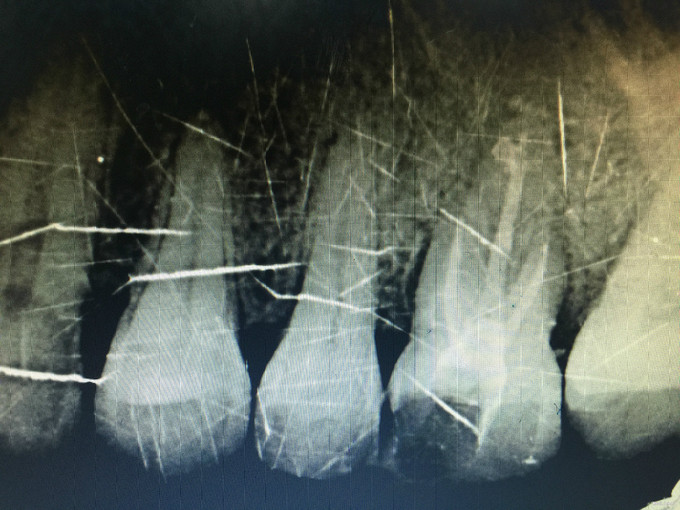

临床检查:26近中龋坏可探及穿髓点,无窦道,探疼(+),冷(++),叩(-),松动度(-),牙周红肿,牙石1度 辅助检查:X线示26龋坏累积髓腔。

诊断:26牙髓炎 治疗:经患者知情同意后,26局麻去腐降牙合,开髓拔髓寻找根管口,建立直线通路,扩通根管,确定工作长度。S3/EDTA凝胶镍钛器械,次氯酸钠冲洗根管,预备至35/04,氢氧化钙诊间封药,一周后复诊,试主尖X线示恰充,试干根管,导AH-PLUS糊剂,VDW热压胶垂直加压根充,术后见根管恰充,暂封调合抛光。树脂充填。